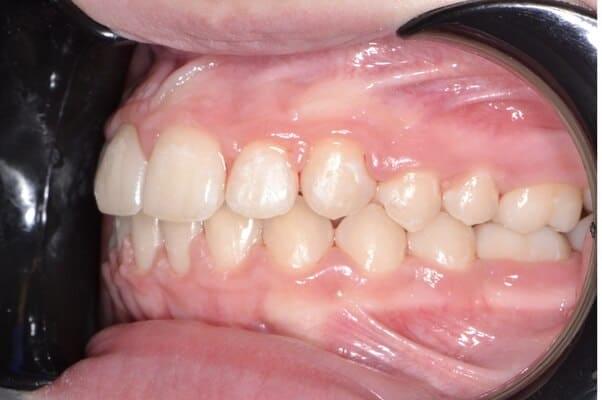

Дівчинка 4,5 років скаржилась на біль в нижньому зубі справа. В зв’язку з високою складністю процедур і значним об’ємом лікування (8 зубів) та після невдалої спроби лікування в звичайному режимі було прийнято рішення про лікування в умовах анестезіологічного забезпечення. Видаленно запалену пульпу (“нерв”) та проведено лікування каналів нижнього зуба ліворуч, цей та сусідні зуби покриті металевими коронками через значний об’єм ураження. Проліковані всі зуби, які потребували допомоги, щоб в майбутньому уникнути болю, дискомфорту та поширення інфекції. Через три години лікування дівчинка може комфортно жувати і не відчувати болю і дискомфорту.